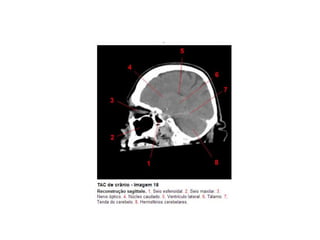

Anatomia E Protocolo Tomografia Computadorizada de Crânio PPT